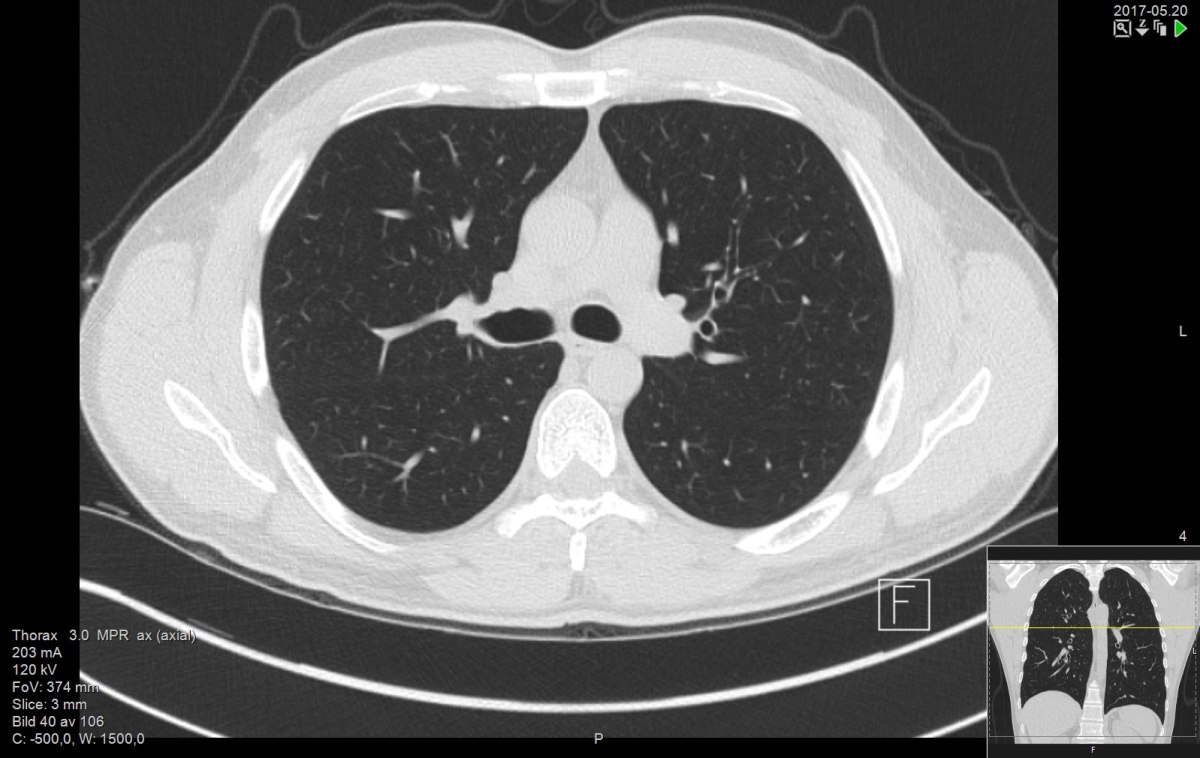

Τομογραφία θώρακος υψηλής ανάλυσης